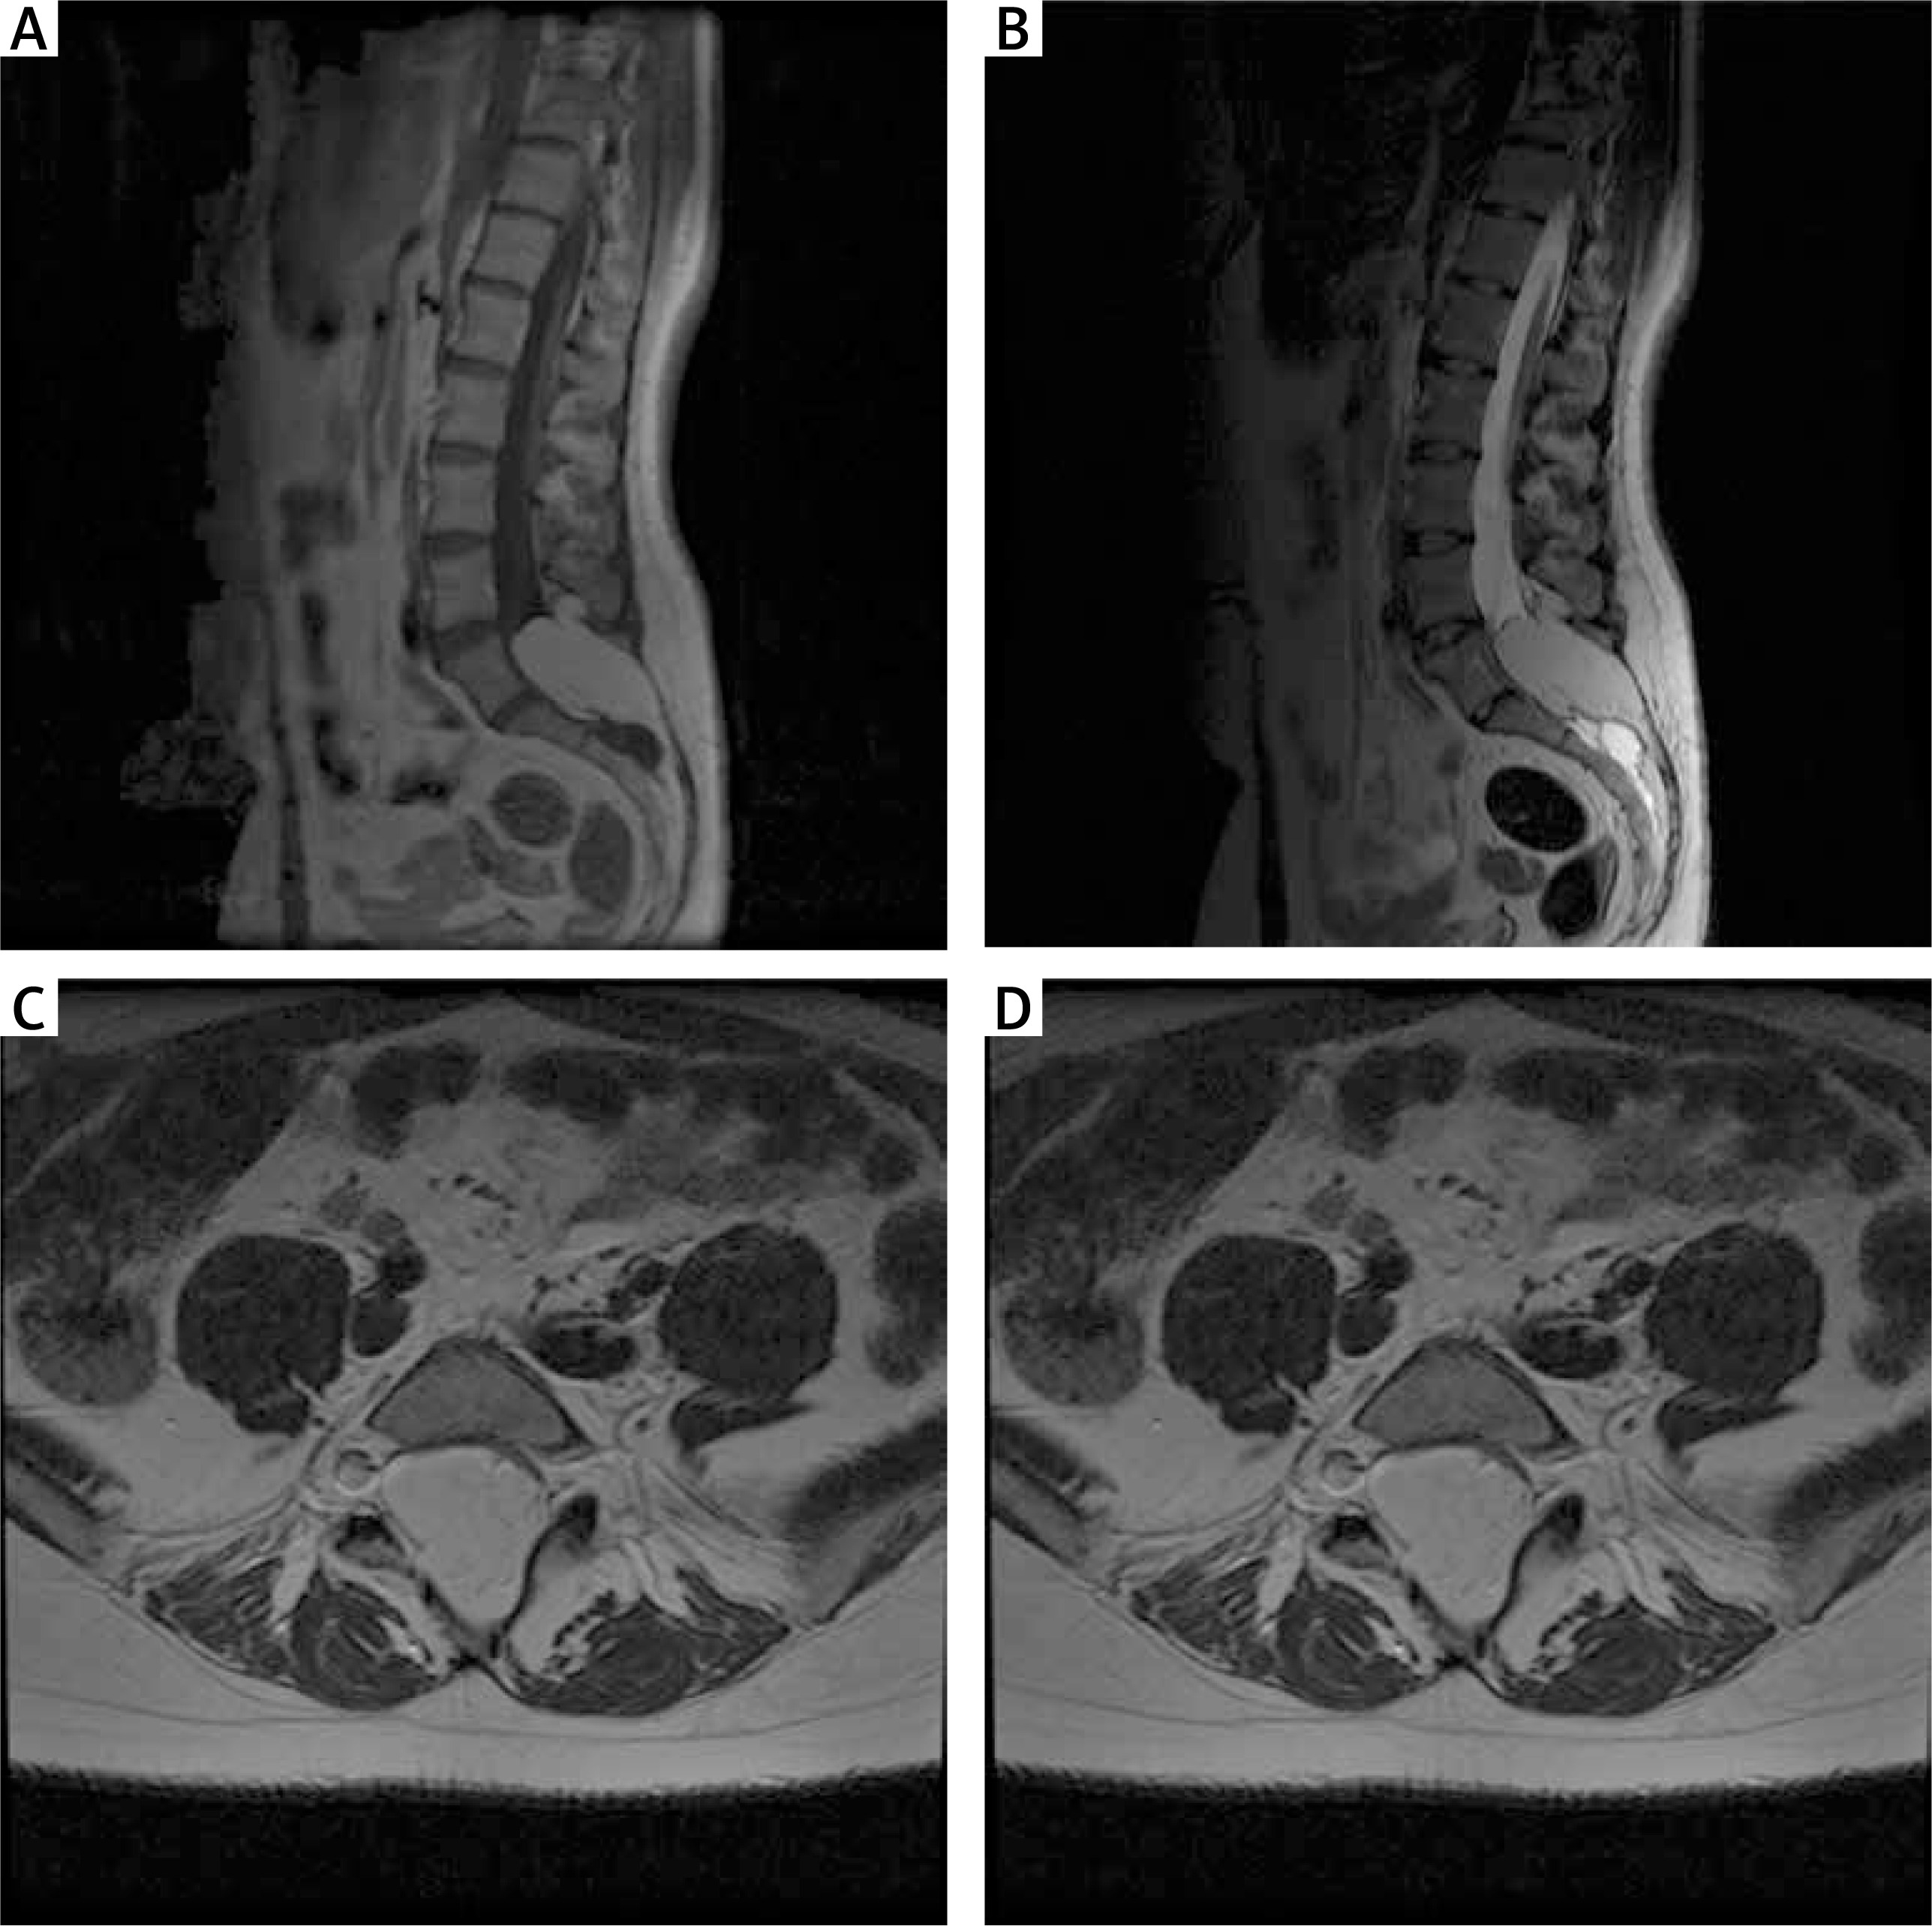

The patient was operated under general endotracheal anaesthesia in the supine position. The skin was incised in the lumbosacral region at 7 cm over the spinous process of L5 and the sacral crest. After removal of the spinous processes of the L5 and S1 vertebral arches, the operating microscope and microsurgical technique were used. The meningeal sac was incised above the site of the adipose tissue exit, and the entire mass of the adipose tissue, 5 cm in diameter with the spinal nerve roots passing through it, was visualized. The adipose had spread beyond the spinal canal into the adipose tissue. The tumour was removed subtotally. Complete resection was not possible because of the overgrowth of the spinal nerves and the consequent risk of their damage. The entoptic thread visible under the operating microscope was thicker than the nerve roots and had a white iridescent colour with connective tissue fibres visible on its surface. After cutting the terminal thread, a reduction in the tension of the nerve elements was obtained. In order to verify the nerve structures, intraoperative monitoring was used: sensory and motor evoked potentials (SSEP) and electromyogram (EMG). The 12 mm long subcutaneous steel electrodes were used for SSEP stimulation and monitoring of lower limbs. EMG was studied using 25 mm electrodes placed in the quadriceps femoris, tibialis anterior, and gastrocnemius muscles, bilaterally. Electrodes were also placed bilaterally in the external rectus sphincter muscles. An electrode was placed on the Foley catheter to monitor the external urethral sphincter. Bipolar stimulation was applied during preparation to assess the functionality of the neural tissue. The potentials evoked by manipulation or stimulation of the monitored nerve roots were processed by the neuromonitoring system into sound signals heard and interpreted by the surgeon. The patient had significant improvement in lower limb mobility and sphincter function. There was minimal improvement in sensation. The pain in the lumbar region remained unchanged. The early postoperative period was complicated by a fluid cyst, palpable subcutaneously and visible on postoperative MRI (Figure 2). The CSF collection was treated with several punctures and evacuation of the fluid. The patient was discharged on postoperative day 14. A scar at the surgical wound site developed 20 days after surgery.

Figure 2

MRI examination in the early postoperative period in the first patient. A – T2-weighted postoperative study with visible fluid cyst. B – T1-weighted contrast-enhanced MR study with visible cyst and partially removed adipoma. C – Axial sections of T2-weighted contrast-enhanced MR study; fluid collection and degree of resection visible

Late postoperative period

The patient had significant improvement in lower limb mobility and sphincter function. There was minimal improvement in sensation. The pain in the lumbar region remained unchanged. The patient was consulted on an outpatient basis 12 months after the surgical treatment. She did not report any recurrence of symptoms and the therapeutic effect remained good. MRI examination showed healed surgical area and subtotally removed adipose tissue (Figure 3).

Figure 3

MRI scan at 12 months after surgery in the first patient. A – T2-weighted MR imaging with a healed surgical approach area. B – T1-weighted MR imaging with variable flip; a properly healed surgical approach area. C – T1-weighted MR imaging, axial sections; healed wound with the visible laminectomy site